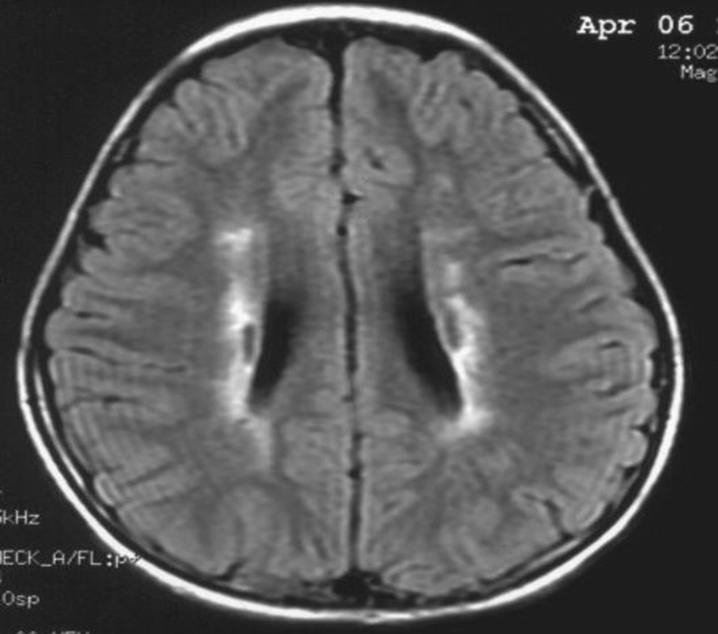

患者:林某某性別:男年齡:8 歲基本情況:出生后3個月臨床和頭部CT檢查診斷為腦癱。8年來病人曾在全國各地接受各種中西醫(yī)治療,病人入院時確診為痙攣性腦癱。治療時間:2005年7月接受干細胞移植手術。

治療前情況:全身僵硬,尖足,交叉,雙手后背,頸部歪斜。不能獨坐、獨站、不能行走,雙手不能持物。言語含糊,面部僵硬。

治療后情況:全身僵硬緩解,尖足和交叉消失,雙手后背緩解,頸部歪斜消失。可以獨坐一個小時,雙手持物好。言語清晰,面部表情自如。